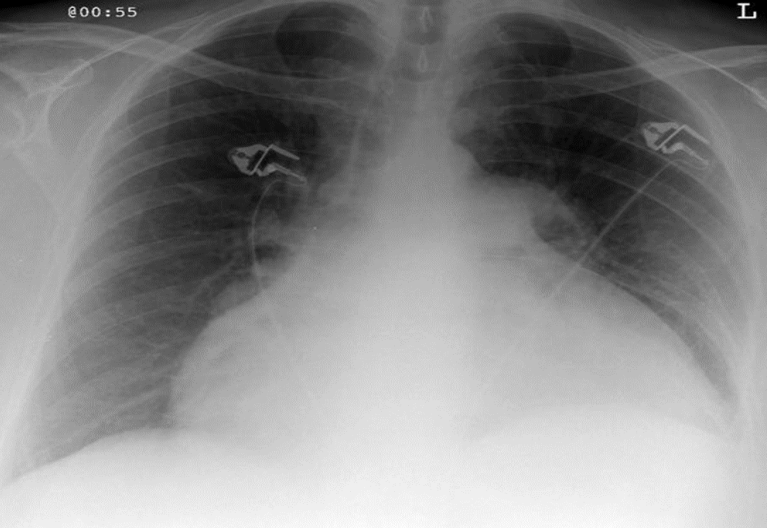

right side peunothorax

tracheal deviation to left

compresed/shifted heart

absent vasculature on right